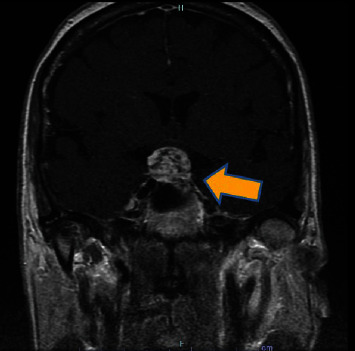

In this report, we present the case of a 71-year-old African-American woman experiencing 2 months of intermittent headaches and episodes of blurred vision. Despite a comprehensive medical history that revealed chronic conditions and previous unrelated surgeries, the initial evaluation appeared to be unremarkable. Following the discovery of a mass on an imaging and a subsequent biopsy, the diagnosis of craniopharyngioma (WHO grade I) was confirmed. However, a brain mass was identified after additional ophthalmologic examination and MRI. This case explores the significance of recognizing atypical presentations of a brain injury that required a specific approach for diagnosis, surgical intervention and treatment, and postoperative care. This case contributes to the constantly evolving understanding of atypical manifestations of tumor characteristics and their complexities, along with the need to develop appropriate patient management strategies and provide optimal outcomes.